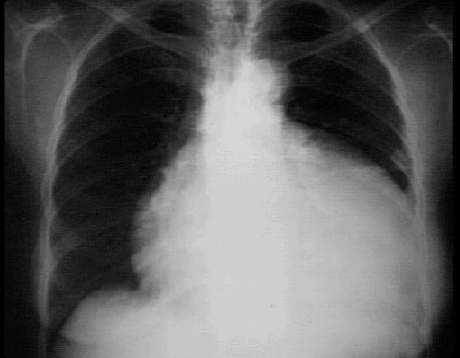

This chest X ray shows a pericardial effusion. This PA view shows a markedly enlarged cardiac silhouette producing a water bottle appearance. Note the neck region of the water bottle formed by the normal aortic shadow. Note also the normal pulmonary vascularity of the lung fields, an important hint that this enlargement of the cardiac shadow does not reflect underlying chamber enlargement.